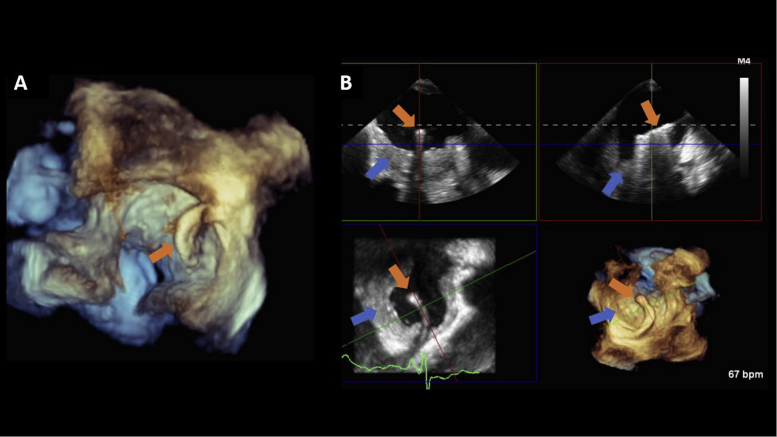

The patient proceeded to have a TEE-guided percutaneous transcatheter biopsy of the mass (Figure 5, Video 7). Following transseptal puncture, three-dimensional (3D) live multiplanar reconstruction was performed to guide the placement of the catheter and biotome over the left atrial mass. However, the biopsies revealed only thrombotic material. The patient became hemodynamically unstable when sedated for the procedure, and the interventionalist was reluctant to do a repeat biopsy. However, the imaging was reviewed again, and the highly suspicious CMR findings prompted a repeat attempt, which revealed a poorly differentiated intimal sarcoma. She was evaluated by cardiothoracic surgery and deemed inoperable due to extensive infiltration of cardiac tissue. Due to her advanced age, she was not considered for cardiac transplantation. She was referred to a sarcoma specialty center where she was treated with docetaxel/gemcitabine. Heart failure symptoms were refractory to chemotherapy and diuresis. The patient passed away 3 months later.

Figure 5.

TEE 3D imaging. Two-dimensional, biplane, and 3D TEE imaging was performed to guide the transcatheter biopsy of the left atrial mass. Following transseptal puncture, 3D live multiplanar reconstruction (MPR) was performed to guide the placement of the Agilis catheter and biotome (orange arrows) over the left atrial mass (blue arrows). Samples were collected from different locations within the mass. (A) A volume-rendered image of the Agilis catheter across the interatrial septum; (B) 3D live MPR shows the catheter as it is being steered toward the left atrial mass. Three-dimensional imaging with live MPR allows for real-time manipulation of all imaging planes (coronal, sagittal, and transverse) to facilitate coaxial imaging of the catheter.